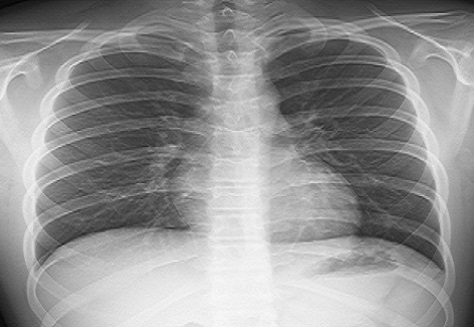

Radiographie du thorax

Elle vise à fournir une visualisation statique des organes et des structures situés dans la poitrine.